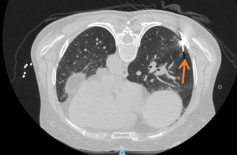

唐中明主任带领团队认真研究,细心评估,考虑:1.右下肺磨玻璃结节随访10月仍存在,2.影像学提示右下肺磨玻璃结节有血管支配供血,虽然结节较小,但仍属于高危结节;3.患者心理负担重,4.患者左上肺腺癌根治术术后,综合考虑要解决右下肺磨玻璃结节首选微波消融术,胸外科一病区团队量身定制了微波消融治疗方案。3月28日,唐中明主任在CT引导下,将一根直径不到2mm的消融针经皮肤精准刺入患者肺部结节病灶内行微波消融术,术后患者皮肤仅留有一细小针眼,患者术后2小时下床活动、正常进食。在胸外科一病区加速康复的照护下,患者恢复良好。

▲消融针定位中